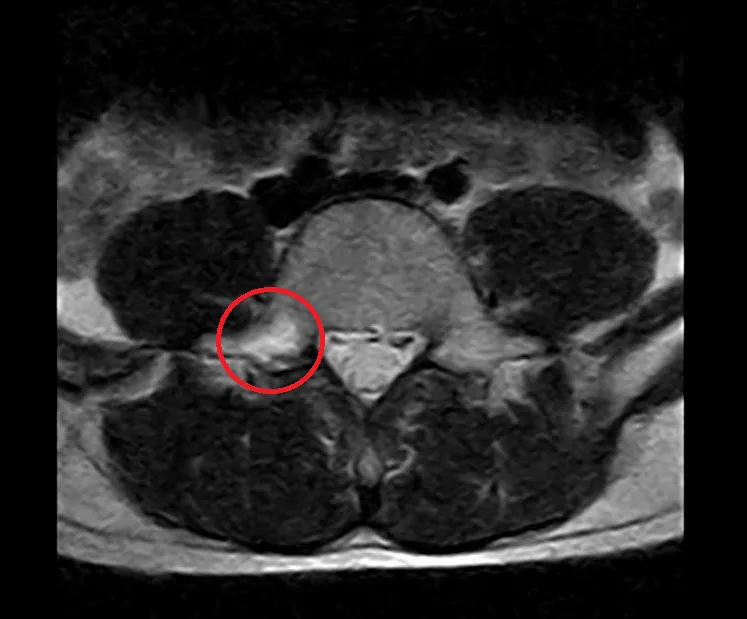

腰椎分離症

Lumbar Spondylolysis